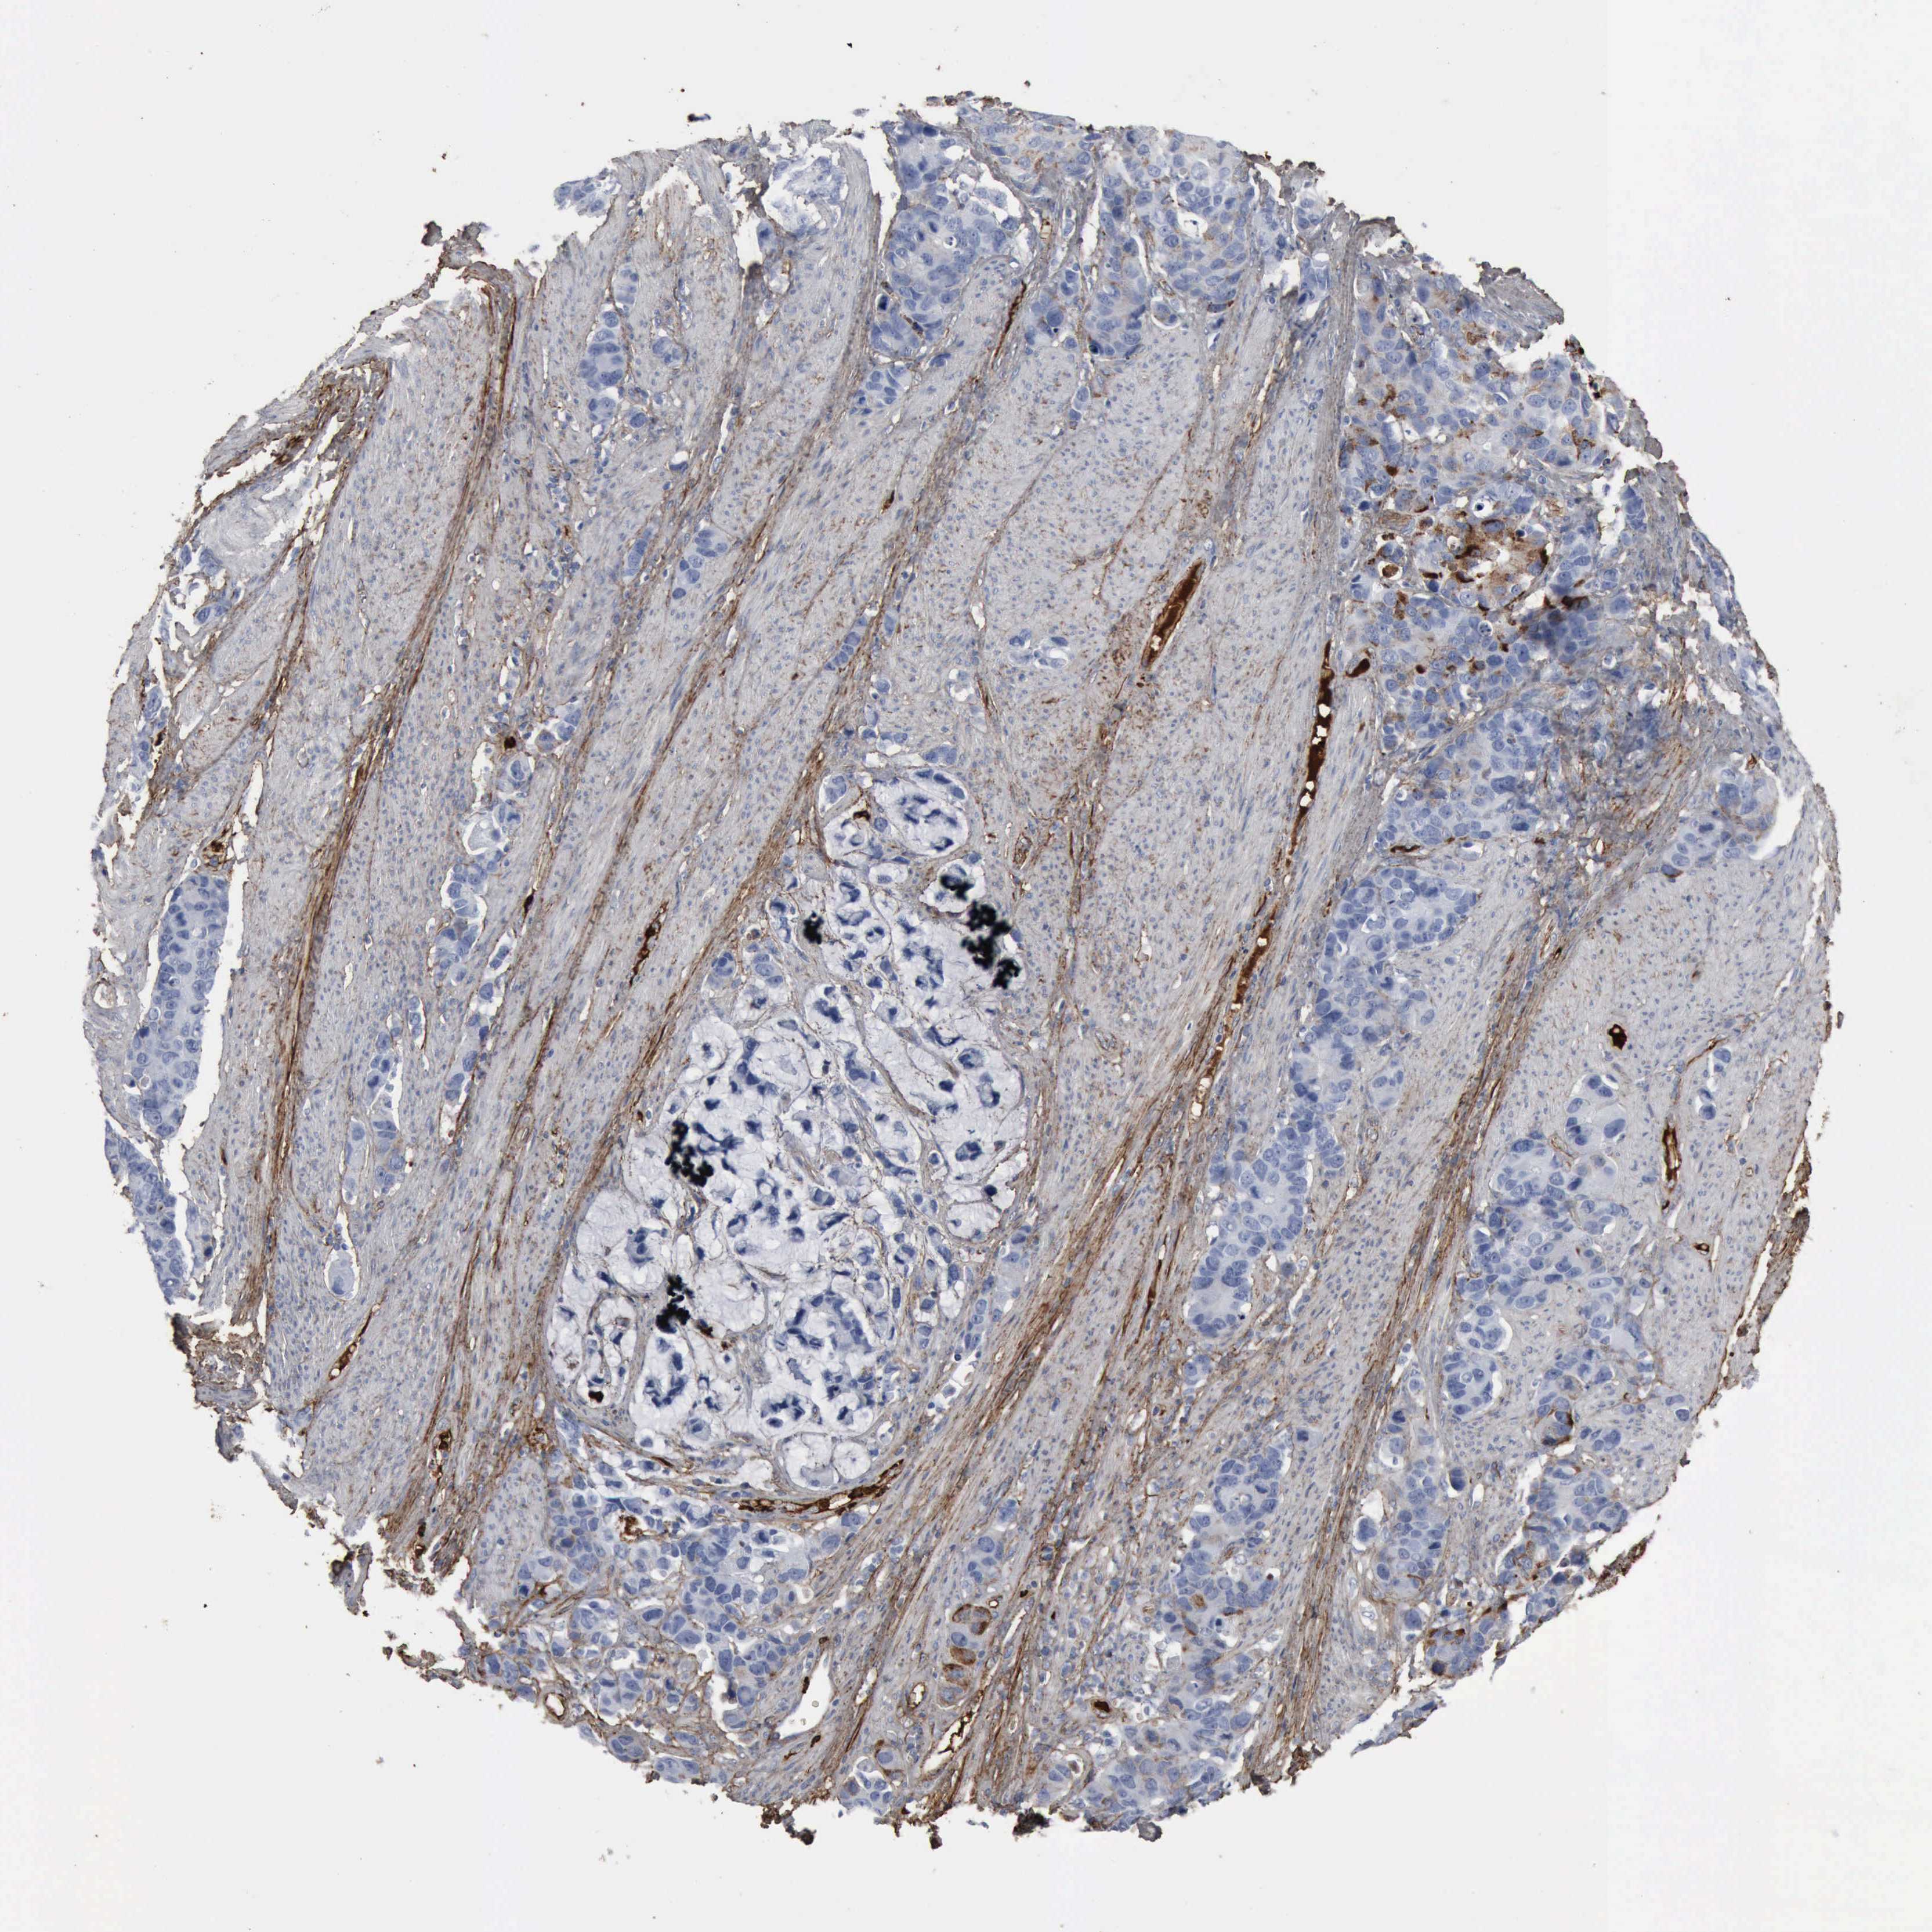

STOMACH CANCER - Protein expressioni

A mouse-over function shows sample information and annotation data. Click on an image to view it in a full screen mode. Samples can be filtered based on level of antibody staining by selecting one or several of the following categories: high, medium, low and not detected. The assay and annotation is described here.

Note that samples used for immunohistochemistry by the Human Protein Atlas do not correspond to samples in the TCGA dataset.

Antibody stainingi

Antibody staining in the annotated cell types in the current human tissue is reported as not detected, low, medium, or high, based on conventional immunohistochemistry profiling in selected tissues. This score is based on the combination of the staining intensity and fraction of stained cells.

Each image is clickable and will lead to virtual microscopy that enables deeper exploration of all samples and also displays staining intensity scores, fraction scores and subcellular localization as well as patient and tissue information for each sample.

Antibody HPA027066

Antibody CAB000126

Staining

High

Medium

Low

Not detected

Intensity

Strong

Moderate

Weak

Negative

Quantity

>75%

75%-25%

<25%

None

Location

Nuclear

Cytoplasmic/membranous

Cytoplasmic/membranous,nuclear

Adenocarcinoma, NOS